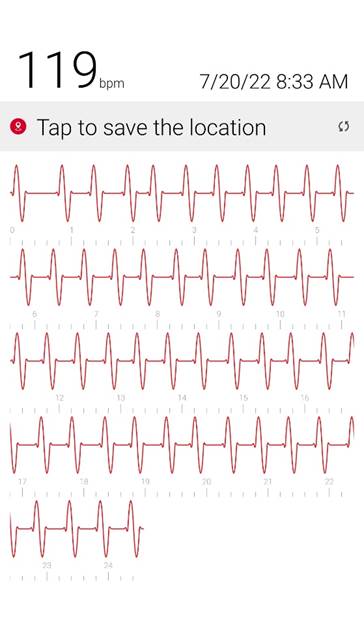

Initial ID consult diagnosed local tetanus based on clinical symptoms and recommended oral Metronidazole 500mg every 6 hours as an outpatient. Autonomic involvement developed with tachycardia and cardiac arrhythmia, along with episodes of sudden sweating. Loud noises made twitching/spasms worsen. Intermittent twitching continued to be present bilaterally in the body, face, jaw & tongue. Symptoms were suppressible with benzodiazepine. Tetanus IM IG 500 IU was recommended and obtained. After initial 2 week course of metronidazole was discontinued symptoms worsened again when patient would walk. Multiple trials of oral Metronidazole 500mg every 6 hours were attempted with some improvement while on the antibiotic but then return and worsening of symptoms again once antibiotic was discontinued.

3) Cardiac Arrhythmia / Heart Block occurs during generalizations

When antibiotic is discontinued or with increased walking, rhythm returns to normal when antibiotic is restarted after a few days.